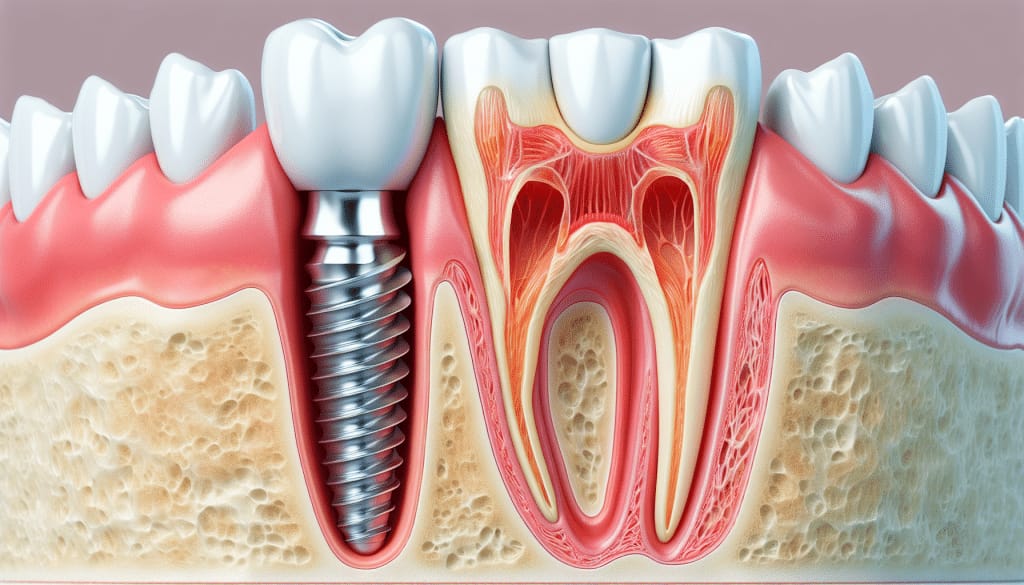

A root canal treatment is a dental procedure used to treat infection or damage inside the tooth, particularly in the pulp (the soft tissue inside the tooth containing nerves and blood vessels). When the pulp becomes infected or inflamed due to deep decay, cracks, or injury, a root canal is needed to save the tooth and prevent further damage

A root canal treatment (also known as endodontic therapy) is a dental procedure used to treat infection or damage in the pulp of a tooth. The pulp is the soft tissue inside the tooth that contains nerves and blood vessels. When the pulp becomes infected or inflamed due to decay, injury, or infection, a root canal can help save the tooth and prevent further damage.